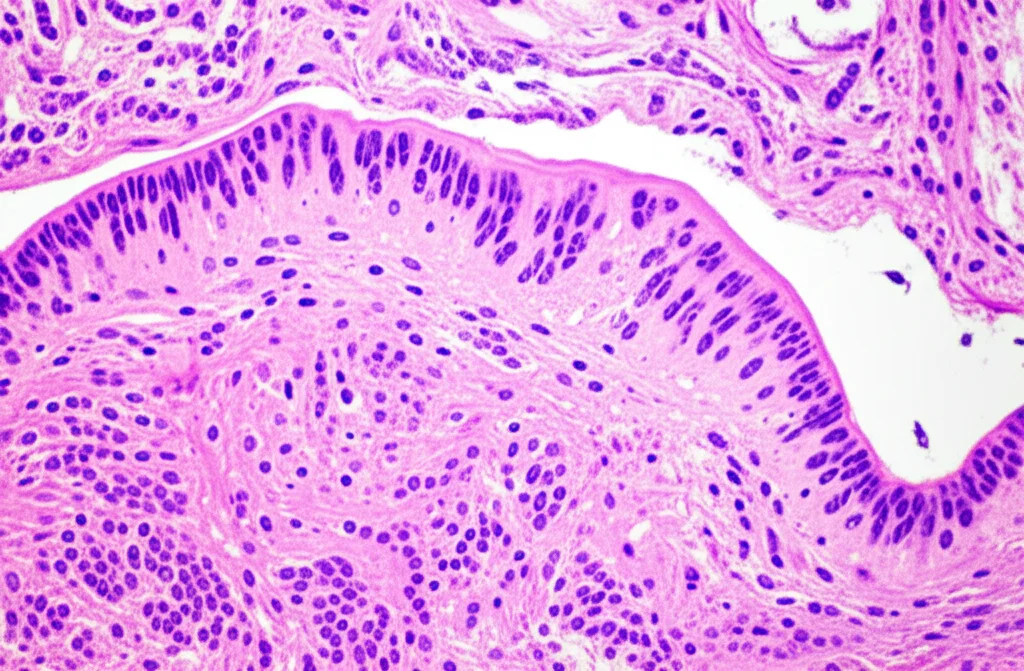

E i polmoni? Cinque giorni dopo l’infezione, abbiamo esaminato i polmoni. I suini Epigraph e WT avevano lesioni macroscopiche quasi assenti. Quelli vaccinati con FluSure XP® mostravano lesioni moderate, mentre i controlli avevano gravi consolidamenti polmonari tipici dell’influenza. A livello microscopico, Epigraph ha mostrato tessuti polmonari e tracheali sani, senza tracce di antigene virale. Il gruppo WT aveva una lieve polmonite interstiziale, ma senza virus rilevabile. Sorprendentemente, il gruppo FluSure XP® mostrava una polmonite interstiziale severa con cellule positive all’antigene virale, nonostante la carica virale nel lavaggio broncoalveolare (BAL) fosse bassa (simile a Epigraph e WT). Questo suggerisce che le lesioni in questo gruppo potrebbero essere più legate a una risposta immunitaria eccessiva (forse un accenno di VAERD?) piuttosto che alla replicazione virale diretta. I controlli, ovviamente, avevano il quadro peggiore, con bronchiolite, polmonite e molto antigene virale.